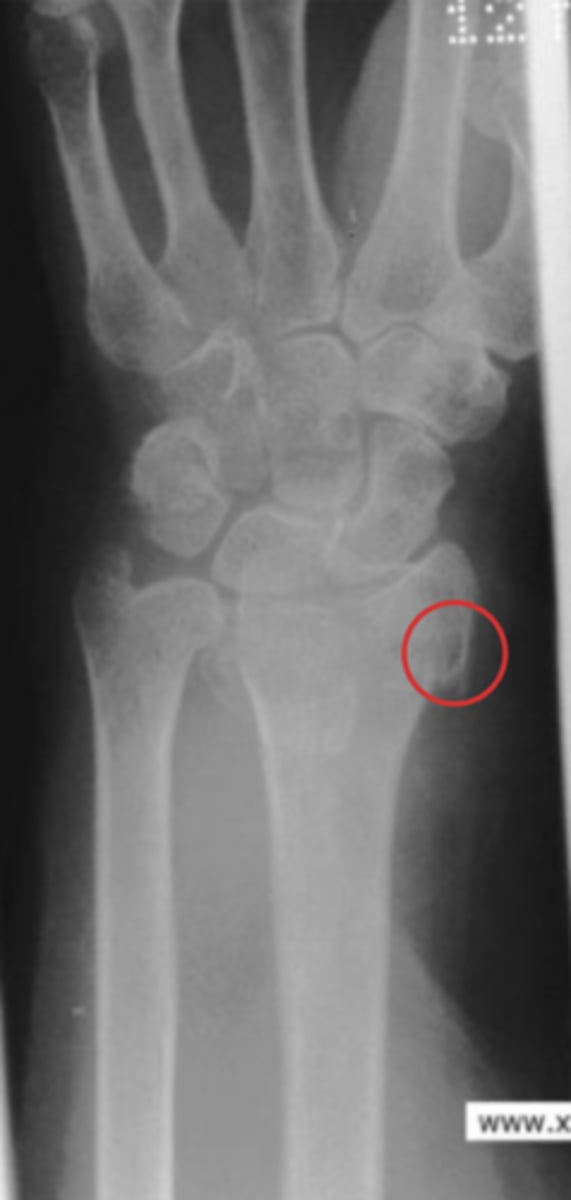

Scaphoid fracture and minor ulnar fracture

What is the issue?

Terry Thomas sign (DISI)